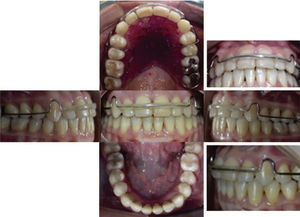

Facially, she presents a concave profile, mesofacial pattern, decreased upper facial third, asymmetry, neutral smile, lip competence and a slightly everted lower lip. Upon clinical examination and intraoral analysis, it was observed bilateral molar class III, a canine class III, a 3mm overbite, -2mm overjet, moderate lower dental crowding, dental midline deviation, ovoid upper and lower arch form, unilateral anterior and posterior crossbite and controlled generalized chronic periodontitis (Figures 3 at 5).

TREATMENT PLAN0.022” slot Roth System appliances with bands in the first and second upper and lower molars would be placed. An interconsultation would be made with the Periodontics Department where scaling and root planning in the lower anterior area would be performed and subsequently, a free gingival graft would be placed. The patient was kept in a maintenance phase of periodontal treatment to continue with the orthodontic treatment.

Orthodontic treatment Phase I of alignment and leveling would begin by placing 0.014”-0.016” NiTi archwires. During Phase II-1, light 2nd and 3rd order movements would be performed with an archwire sequence from 0.016” × 0.016” NiTi- 0.017” X 0.025” SS. In Phase II-2 retraction of the lower anterior segment would be performed with a 0.019” × 0.025” DKL archwire. At this point of treatment, the case would be re-assessed to determine whether the treatment continued with orthodontics or orthodontics and orthognathic surgery.

TREATMENT PROGRESSTreatment was begun with the placement of fixed appliances, 0.022” slot Roth system, in the upper arch. The Department of Periodontics conducted the scaling and root planning in the lower anterior area and subsequently, placed a free gingival graft. A month later fixed appliances were placed in the lower dental arch thus beginning the leveling and alignment with the corresponding archwires (Figure 6). Three segments were formed throughout this phase: one anterior segment and two posterior ones. After the segments were formed a single keyhole loop (SKL) archwire was placed in the lower arch maintaining a segment with ligature wire from lower first molar to canine on both sides. The archwire was activated in the following appointment with a Suzuki retroligature to begin space closure (Figure 7A).